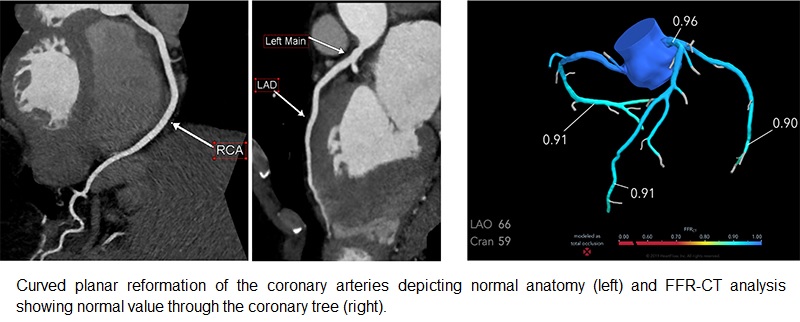

Η αναίμακτη ή αξονική στεφανιογραφία είναι μια μη επεμβατική μέθοδος που χρησιμοποιεί αξονικό τομογράφο υψηλής ανάλυσης για να απεικονίσει τις στεφανιαίες αρτηρίες — χωρίς καθετήρα και χωρίς νοσηλεία.

- Δίνει πληροφορίες όχι μόνο για τη στένωση, αλλά και για τη σύσταση των πλακών (μαλακές ή ασβεστωμένες).